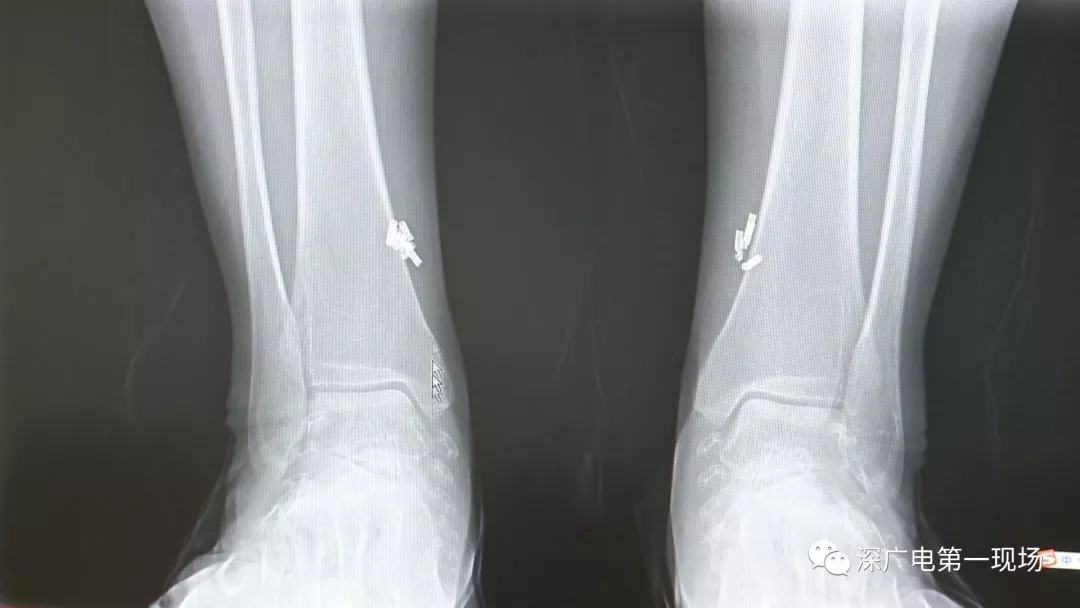

深圳一女子全身被植入彈簧圈,數(shù)量多到驚人!竟是為治這病…

出于保護患者,我們沒有直接采訪,但是通過醫(yī)生的介紹,記者了解到,病人是個36歲的女性,2歲開始就有癲癇病史,而且藥物治療也并不見效。

多方打聽之后,在山東某診所用全身埋彈簧圈的方式治療癲癇。陶主任介紹,這樣的方式想要治愈,那幾率也等同于撞大運??!

陶醫(yī)生介紹,目前并沒有看到一個特別正規(guī)的報道,說這種方法到底治了多少病人,總體的治愈率是多少,有多少病人能夠發(fā)作減輕,這個是沒有看到。